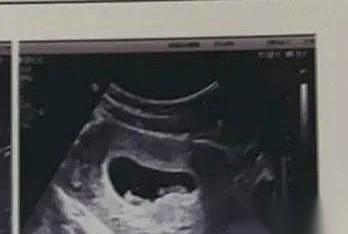

“月份大了会越来越严重。” 就这一句话,一个穿着白大褂的人,轻飘飘的一句话,就把我和我那俩未出世的闺女,一起推下了悬崖。 我甚至都来不及反应,意志力“啪”一下,就断了。 我现在躺在床上,总觉得家里还飘着那股医院的味道。一周了,我亲手终结了她们。我那两颗B超里挤在一起,像小花生米一样的双胞胎女儿。 36岁,二胎。 听着是不是觉得特有经验,特皮实? 我当年生我儿子,好家伙,从产房自个儿走出来的,健步如飞。我以为这次也一样。 结果呢? 我错了。身体用最残酷的方式告诉我,今时不同往日。 从吃不下饭,到胃里像被硫酸烧,再到呼吸困难……我感觉自己不像个孕妇,像个被判了无期徒刑的囚犯。 躺在床上,连被子都像一座山压着我喘不过气。说一句话,要歇半天。 我不是矫情,是真的感觉自己快死了。 那时候哪还有什么母爱啊,我就是个快要溺死的人,而她们,是我身上越来越沉的负担。 我当时就觉得,我不要了。我不行了。我不可能辞职,我不能这么废人一样躺到生。 你看,人就是这么自私。在极限的痛苦面前,什么母性,什么骨肉,都让位给了“我想活下去”。 可笑吧。 我亲手关掉了身体的警报,然后迎来了灵魂的,一辈子的酷刑。 当她们离开我身体的那一刻,那种排山倒海的母爱和悔恨,瞬间就把我淹没了。 我疯了一样地想,我怎么能这么干?我怎么能因为自己难受,就剥夺她们看太阳的权利? 我才是那个最垃圾,最残忍的人。 身体的痛苦是有尽头的,而心里的这个窟窿,一辈子都填不上了。 我恨我自己。